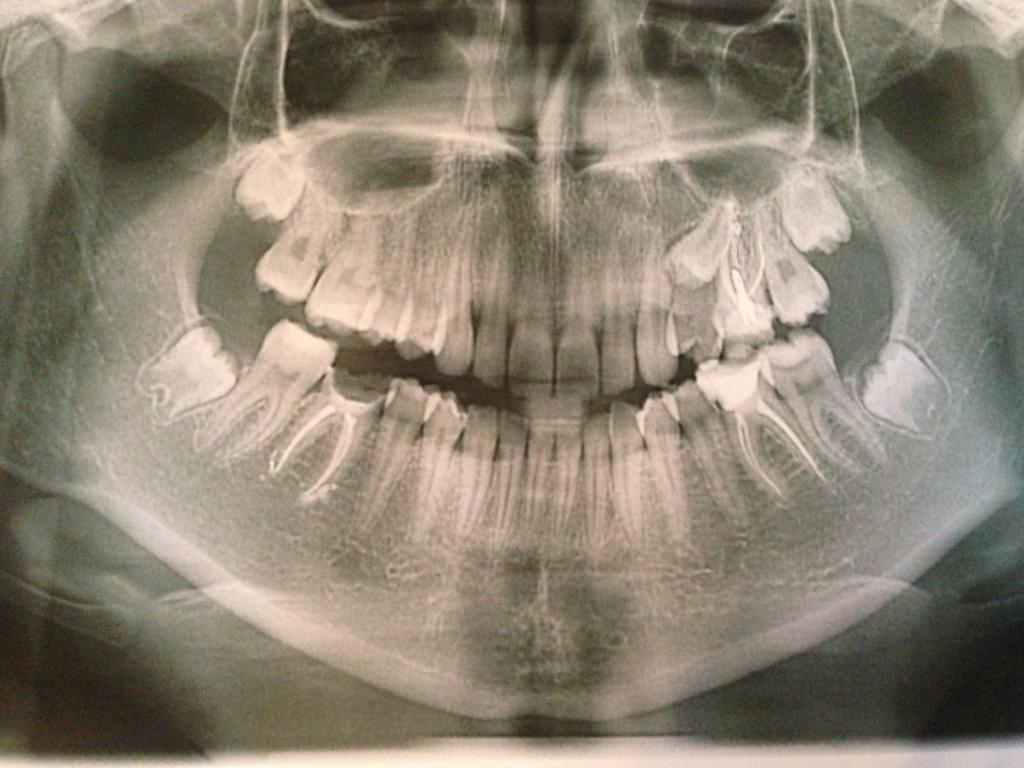

Нажмите на изображение для увеличения

Название: image.jpg

Просмотров: 49

Размер:	88.5 Кб

ID:	5660051Терапевт лечила и никогда не видела что 5-ка в десне.Я решила сделать керамические вкладки на 6-ки,сделали снимок и увидели 5-ку.Что посоветуете?если удалить 6-ой,можно брекетами 5-ку поставить на его место?

Терапевт лечила и никогда не видела что 5-ка в десне.Я решила сделать керамические вкладки на 6-ки,сделали снимок и увидели 5-ку.Что посоветуете?если удалить 6-ой,можно брекетами 5-ку поставить на его место?

Делайте коронку на шестерку. А пятерка пускай про запас. Вытянуть, если и возможно, то никогда не поздно.

мне Ваша версия большего всего нравиться,удалять крайне не хочется. 5-ка уже начинает прорезаться с небной стороны за 6-м,если она там будет не будет изменений в прикусе и т.д ?

О... Начинает прорезываться...

Конечно будут изменения... Появится еще один зуб...)))